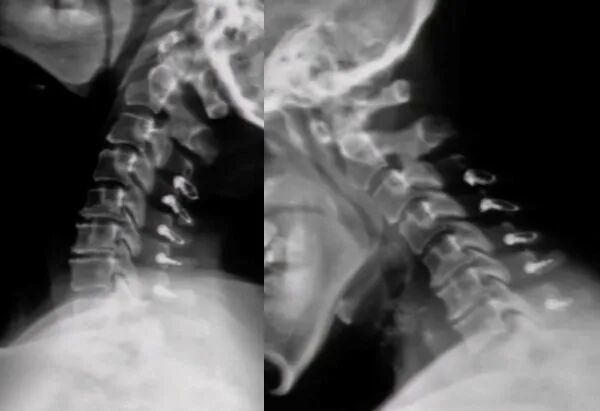

This product is indicated for internal fixation in cervical spine surgery, used for sublaminar and interspinous fixation. It is applicable to segments C1-C7 and can be used alone or in combination with other spinal internal fixation system products of the same system manufactured by the company using titanium materials.